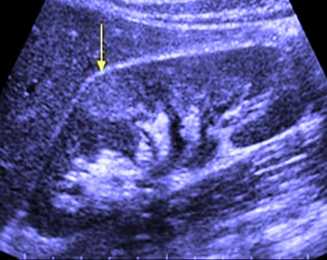

Эхопризнаки острого пиелонефрита на УЗИ, отражённые на картинке:

- появление бугристости, связанной с инфильтрацией лейкоцитами;

- отёк (экссудация), в результате которого происходит увеличение. Нормы размера органа по УЗИ следующие: длина - 10-12 см, ширина - 5-6 см, толщина - 4-5 см, касаемо паренхимы - 1,5-2,5 см. Также определяется разница в размерах правой и левой почек, которые не должны отличаться более, чем на 2 см. Разница может колебаться в зависимости от роста у взрослого, допустимо некоторое увеличение и расширение лоханки при беременности, у ребенка - в зависимости от количества лет, у пожилого человека несколько атрофируется паренхима (толщина уменьшается примерно в 2 раза);

- нарушается чёткость деления ткани внутренней среды на корковое и мозговое вещество, происходящее вследствие отёка и искажения эхогенности;

- при акте дыхания нет изменения положения почки в забрюшинном пространстве, которое в норме присутствует;

- возможен рефлюкс мочи из мочеточника в чашечно-лоханочную систему, что и способствует инфицированию;

- изменяется эхогенность ткани почки, это связано с экссудацией и инфильтрацией. Причём снижается она при диффузном про, а повышается - при очаговом.

Эхопризнаки острого пиелонефрита на УЗИ